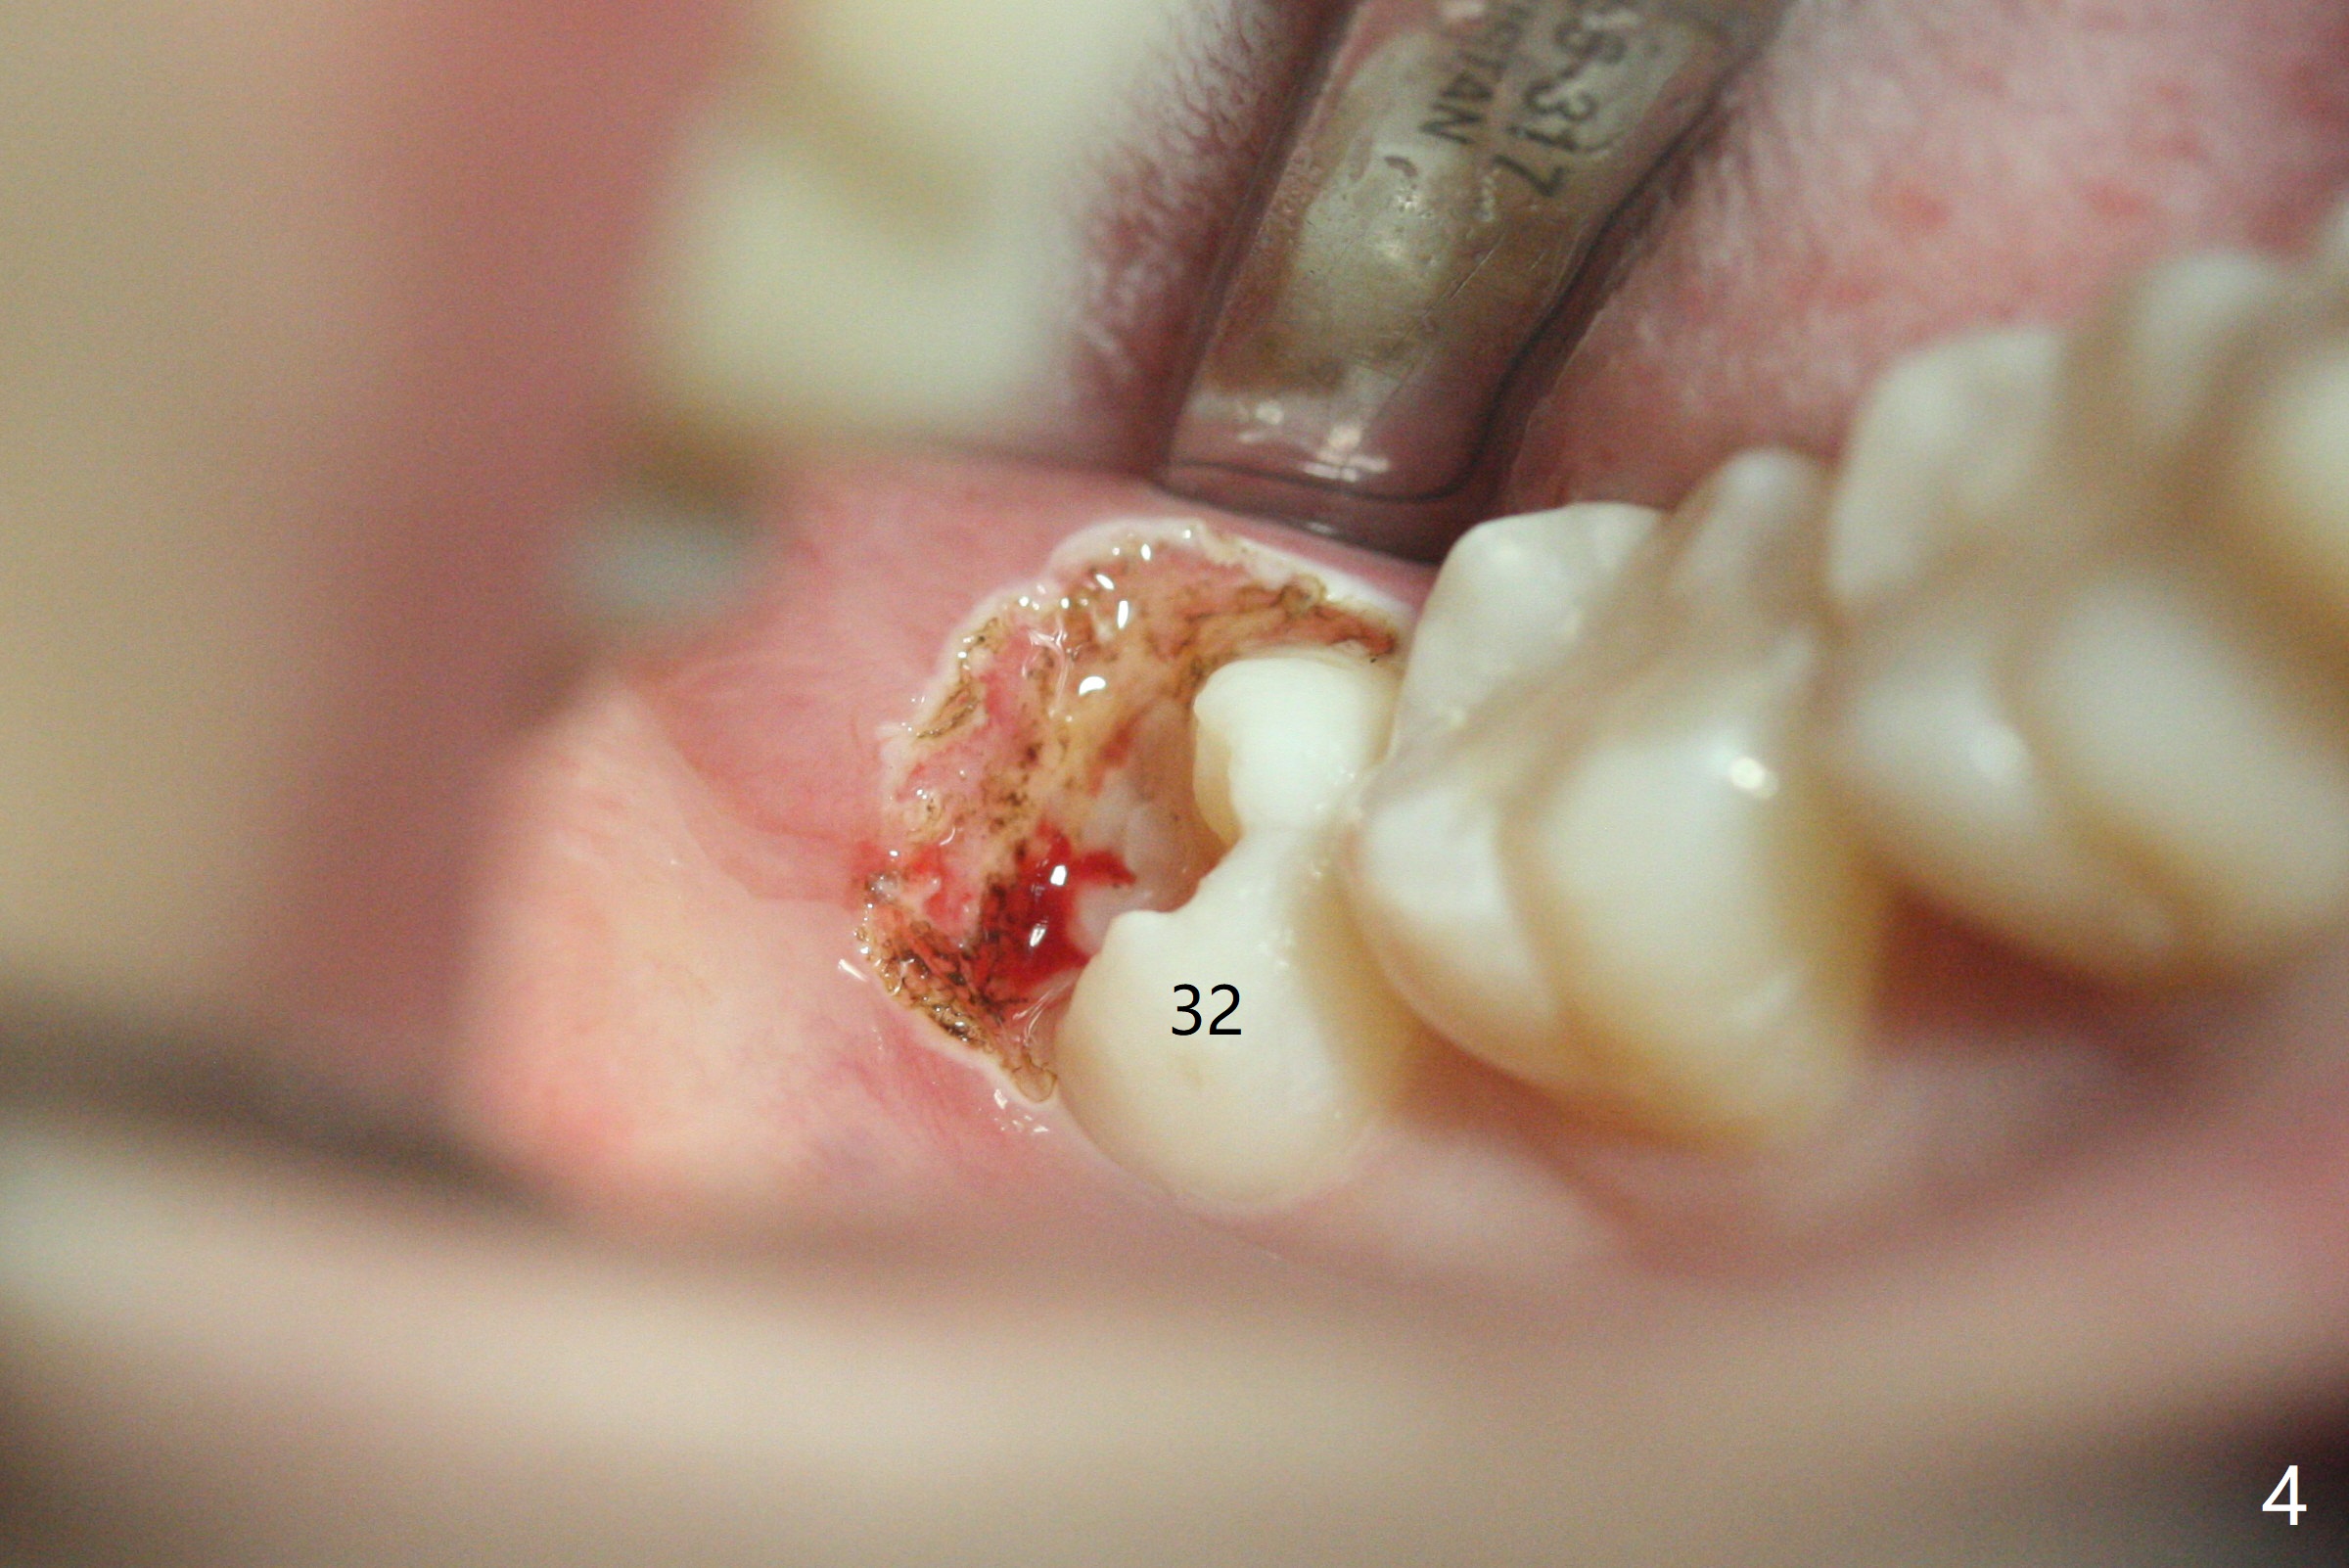

19岁女抱怨右下智齿远中龈下食物坎塞,不希望拔除,因为缺牙太多:先天性缺失一个下切牙,为了矫正又拔除4个双尖牙(图一)。临床检查32号牙远中牙龈覆盖(图二:*),而17号牙萌出不多(图三),没有食物坎塞史。局麻下,使用Diode Laser (Picasso)切除牙龈直到智齿远中咬合面暴露(图四)。术后突然意识到为了防止牙龈重新覆盖,必须做crown lengthening,也就是切除远中骨质(图五(黑色),与图一’对比),是吗?随访时利用Shining口扫记录,拍摄角度好。